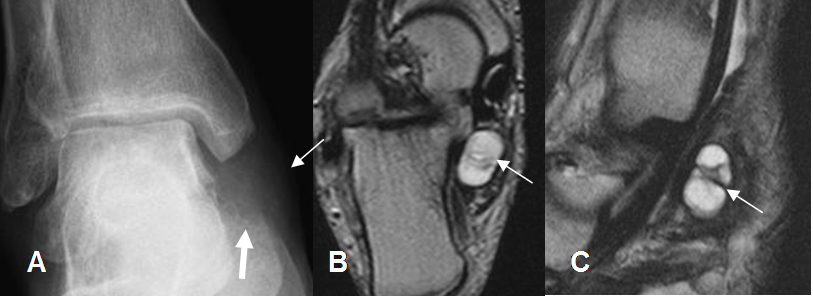

Fig 218 C. Sindrome del tarso.

A: Rx AP. Prominencia de tejidos blandos por debajo del maléolo interno (Flecha delgada), que erosiona en calcáneo. (Flecha gruesa).

B: RM axial y C: RM sagital en T2. Lesión ovalada, de consistencia líquida, en relación con el tendón del tibial posterior, que ocupa el canal del tarso, por ganglión.